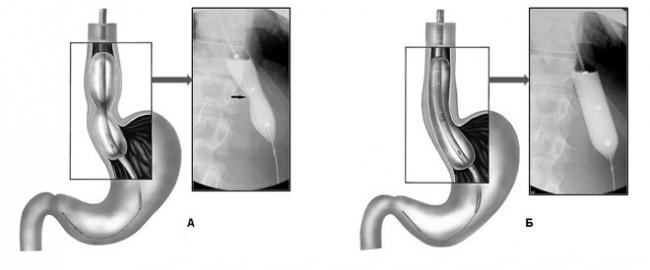

Лечение в случаях тяжелого нарушения глотания осуществляется либо путем расширения места перехода в желудок с помощью баллона, в который под давлением нагнетают воздух (пневмокардиодилатация), либо путем частичного рассечения спазмированных мышц кардиального отдела пищевода с помощью эндоскопа.   Эффективность пневмокардиодилатации пищевода при ахалазии, составляющая от 60 до 100 %, зависит от величины диаметра баллонов-расширителей, продолжительности заболевания, возраста больных.   При наличии противопоказаний к проведению пневмокардиодилатации и хирургического лечения используют введение ботулинического токсина в нижний сфинктер пищевода. Временное облегчение дают и лекарственные препараты, уменьшающие спазм пищевода.

Баллонная дилатация

При ахалазии терапия также может проводиться с помощью баллонной дилатации (расширения). Это специальный эндоскопический инструмент, который врач вводит в пищевод и желудок. Эта процедура механически расширяет суженную нижнюю пищеводную мышцу.

Баллонная дилатация считается наиболее эффективным неоперативным методом лечения ахалазии: после однократного введения признаки нарушения глотания в большинстве случаев улучшаются на несколько месяцев, у половины — даже на несколько лет. Тогда может потребоваться повторная дилатация.

Преимущество лечения ахалазии баллонной дилатацией заключается в том, что процедура выполняется во время рефракции пищевода и желудка, и не требует оперативного вмешательства. Однако, во время лечения могут возникнуть осложнения: во время дилатации может разорваться пищевод (3%).

Пневматическая кардиодилатация при ахалазии пищевода состоит из расширения нижнего клапана с одновременной подачей воздуха или жидкости под высоким давлением. На практике это выглядит так: в пищевод вводят баллон под контролем флюороскопии. После того как баллон достигает диафрагмы, его раздувают. Способ лечения эффективен в 75% случаев, однако есть большой риск появления побочного эффекта в виде ГЭРБ.